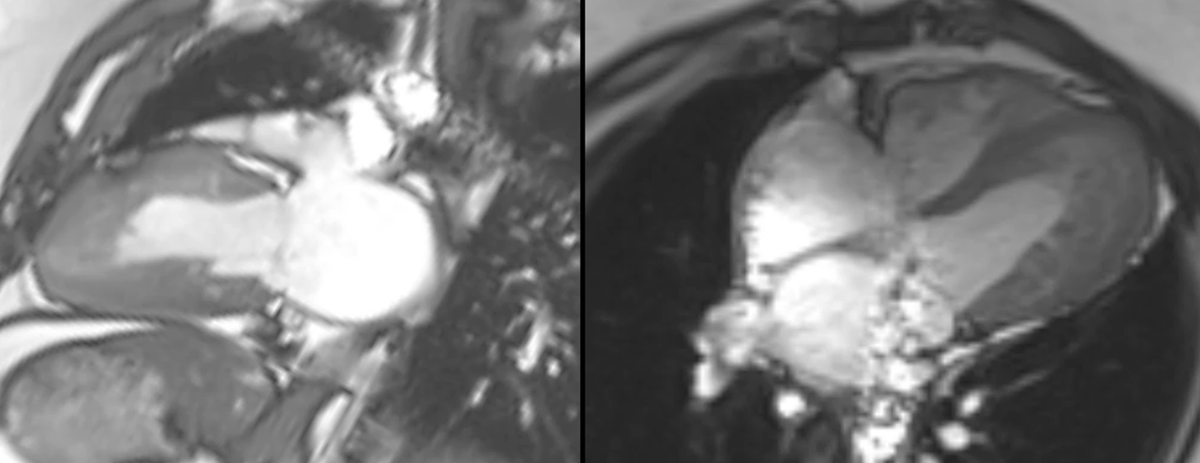

LVNC: Emerging concepts